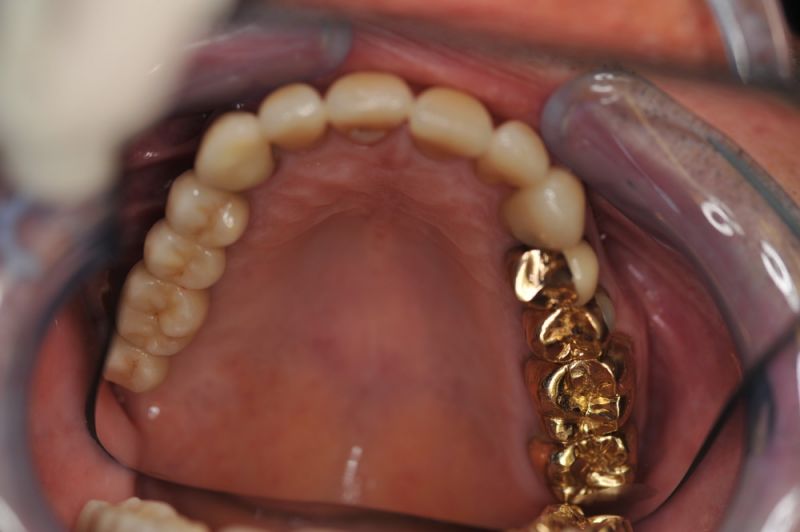

Rekonstruierter Kieler Patient im Recall

Dem Patienten geht es dental gesehen gut.

Die funktionstherapeutische Rekonstruktion befindet sich seit 17 Jahren im Munde des Patienten.

Gemeinsam ist man der Auffassung, dass sich heute zum Glück auszahlt, dass man beizeiten die Fundamente im Mund geschaffen hat, von denen der Patient heute im Alter zehrt.